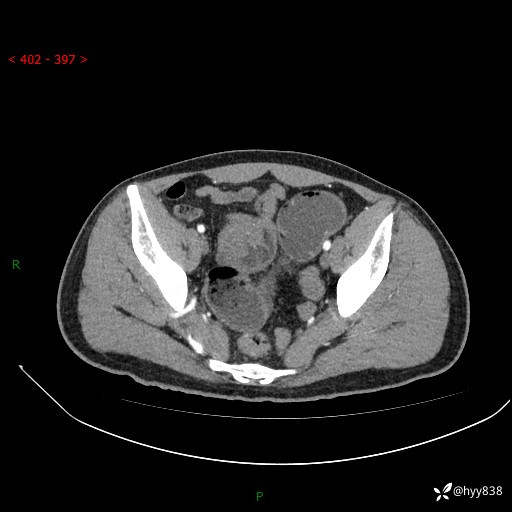

年轻男性,腹痛5月余。除了肠梗阻,你还能看到什么---结果公布~

现病史:患者于5月前无明显诱因开始出现腹痛,上明显,为间断性胀痛不适,无畏寒发热,无心慌气促等特殊不适,遂来我院。我院门诊遂以“腹痛原因待查”收入我科。 起病以来,患者精神、饮食、睡眠欠佳,大小便正常。体力体重无明显变化。

腹部CT增强扫描(动脉期+静脉期)